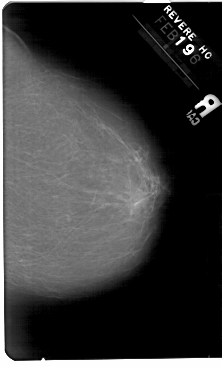

A_1346_1.LEFT_CC

LEFT_CC LINES 5476 PIXELS_PER_LINE 3166 BITS_PER_PIXEL 12 RESOLUTION 43.5 OVERLAY